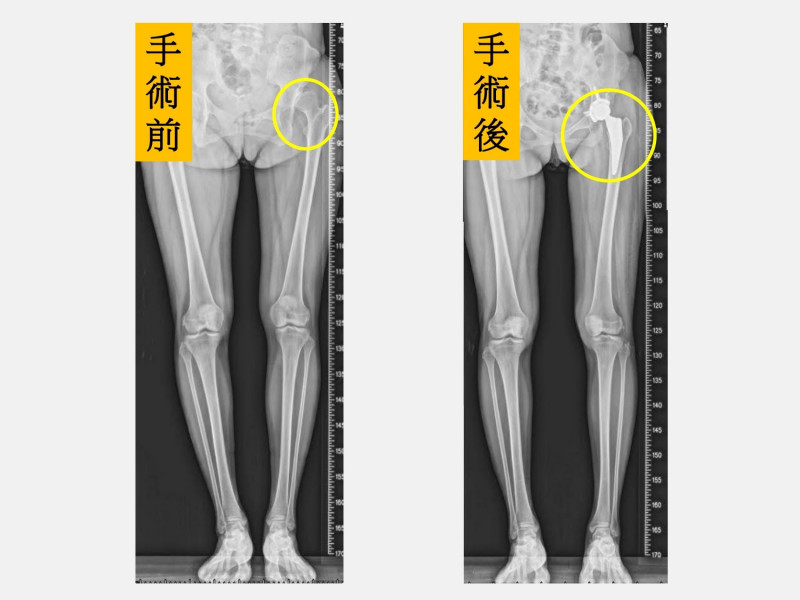

〔記者陳建志/台中報導〕34歲的陳小姐因左側髖關節發育不良,幼兒園和小學時分別接受過2次髖關節截骨矯正手術,但術後多年來走路始終覺得卡卡、疼痛,隨著小孩上小學經常要陪著參加活動,讓她常痛到力不從心,前往骨科求診後,醫師安排「微創正前開髖關節置換手術」治療,經過2個月的肌肉訓練,幾乎恢復正常生活,讓她開心人生重回正軌。

黃贊文表示,陳小姐左側髖關節和大腿因曾經手術2次有著長達30公分疤痕,肌肉也有明顯的萎縮,因此建議進行「微創正前開髖關節置換手術」,手術當天下午麻醉藥效一退,就開始練習騎腳踏車運動,原以為會很痛,但完全沒有痛的感覺,且2隻腳也恢復成一樣長,讓她相當開心。